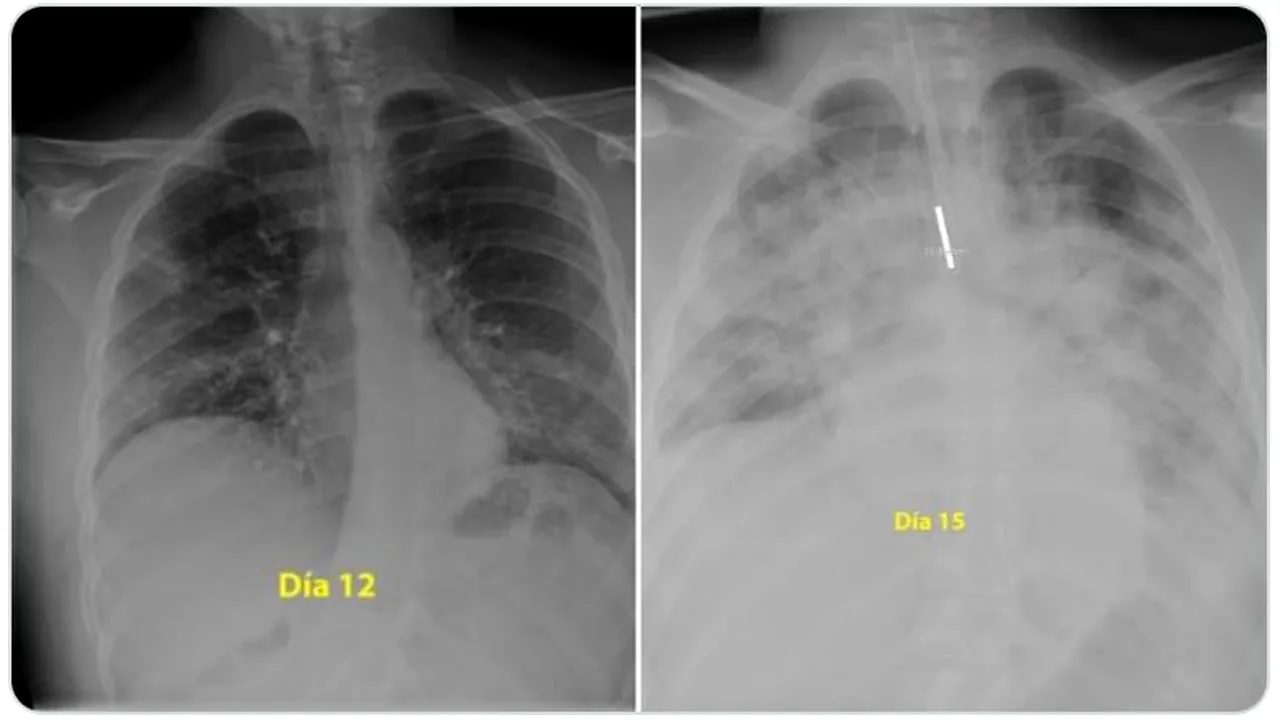

Un renumit medic pneumolog din Spania a făcut publice pe rețeaua de socializare Twitter două radiografii care arată cum a acționat noul coronavirus asupra plămânilor unui tânăr de 28 de ani. Pacientul a suferit o formă gravă de Covid-19, iar în numai trei zile virusul SARS-CoV-2 i-a „mâncat” ambii plămâni!

„Pentru cei care cred că sunt nemuritori și continuă să iasă în parc fără să acorde atenție ordinului de a rămâne acasă, acestea sunt radiografiile unui băiat de 28 de ani intubat la Terapie Intensivă în spitalul meu, pentru #coronavirus. Indiciu: plămânii sunt negri, albul este pneumonie”, a scris medicul pe Twitter.

Prima fotografie a fost realizată în a 12-a zi de boală, iar cea de-a doua, după alte trei zile. În imagini se văd ambii plămâni măcinați de noul coronavirus, iar concluzia este că infecția poate face mult rău și tinerilor, nu numai vârstnicilor.

Beatrice Mahler, managerul Institutului de pneumoftiziologie Marius Nasta, din București, a comentat la Digi 24 cele două fotografii: „E vorba de sindrom de depresie respiratorie acută, este forma severă de pneumonie, care necesită intubație, ventilație mecanică. Din păcate, răspunsul este da, atât de repede și de dramatic li se întâmplă nu numai bătrânilor, ci și tinerilor, tuturor. Vârsta poate să fie un avantaj, în sensul că poate să ajute să depășim acel moment, dacă suntem într-o secție de terapie intensivă, suntem ventilați mecanic, pentru că toate celelalte organe se presupune că sunt sănătoase și pot să susțină momentul critic prin care trece organismul. De aceea, rata de mortalitate este mai mare la cei vârstnici, pentru că boala apare pe un organism bolnav, cu o inimă care are probleme, un ficat bolnav, și atunci depășirea momentului este critică”.